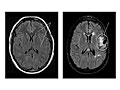

Magnetic resonance imaging (MRI) is a test that uses a magnetic field and pulses of radio wave energy to take pictures of the head. In many cases, MRI gives information that can't be seen on an X-ray, ultrasound, or computed tomography (CT) scan.

For an MRI of the head, you lie with your head inside a special machine (scanner) that has a strong magnet. The MRI can show tissue damage or disease, such as infection or inflammation, or a tumor, stroke, or seizure. Information from an MRI can be saved and stored on a computer for more study. Photographs or films of certain views can also be made.

Magnetic resonance imaging (MRI) is a test that uses a magnetic field and pulses of radio wave energy to take pictures of the head.

Magnetic resonance imaging (MRI) of the head

Normal:

All structures of the head-the brain, its vessels, spaces, nerves, and surrounding structures-are normal.

No abnormal growths, such as tumors, in or around the brain are present.

No bleeding, abnormal blood vessels (AV malformations), abnormal pockets of fluid, blockage in the flow of blood, or bulges in the blood vessels (aneurysm) are present.

No signs of infection or inflammatory disease, such as encephalitis or meningitis, are present.